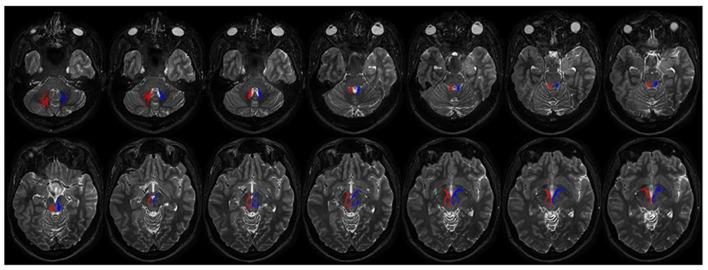

The connections between the cerebellum and basal ganglia were assumed to occur at the level of neocortex. However evidences from animal data have challenged this old perspective showing extensive subcortical pathways linking the cerebellum with the basal ganglia. Here we tested the hypothesis if these connections also exist between the cerebellum and basal ganglia in the human brain by using diffusion magnetic resonance imaging and tractography. Fifteen healthy subjects were analyzed by using constrained spherical deconvolution technique obtained with a 3T magnetic resonance imaging scanner. We found extensive connections running between the subthalamic nucleus and cerebellar cortex and, as novel result, we demonstrated a direct route linking the dentate nucleus to the internal globus pallidus as well as to the substantia nigra. These findings may open a new scenario on the interpretation of basal ganglia disorders.

小脑与基底神经节之间的连接曾被认为发生在新皮层水平。然而,动物数据的证据对这一旧观点提出了挑战,显示出连接小脑与基底神经节的广泛皮质下通路。在这里,我们通过使用扩散磁共振成像和纤维束成像技术,测试了人类大脑中小脑与基底神经节之间是否也存在这些连接的假设。对15名健康受试者使用3T磁共振成像扫描仪获得的约束球形反卷积技术进行分析。我们发现丘脑底核与小脑皮质之间存在广泛连接,并且作为新的结果,我们证明了一条将齿状核与苍白球内部以及黑质相连的直接路径。这些发现可能为基底神经节疾病的解释开辟一个新的局面。